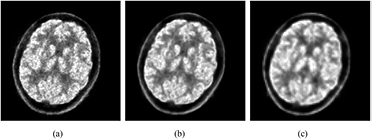

Figures 13(a)–(c) show human brain images of a slice from a healthy volunteer given 11C-MeQAA, with reconstruction (a) in the HR-mode without post-smoothing, (b) in the HR-mode with post-smoothing, and (c) in the HS-mode without post-smoothing, respectively. All 62 min acquisition data were used for the reconstruction. The total true coincidence counts, including scatter events, for image reconstruction were 534 M counts. The HR-mode image (a) appears to be of high resolution, if slightly noisier than the HS-image (c), given the small voxel size of the image matrix and lack of post-smoothing. Therefore, block-matching and 4D filter (BM4D) (Maggioni et al 2013) was applied to the image in (a) for post-smoothing, to derive a denoising image (b). Figure 14 shows 18F-FDG (a) rat and (b) mouse images in the transverse, coronal, and sagittal directions. For image reconstruction, all 15 min acquisition data for the rat and the last 15 min of data from among the 60 min acquisition data for the mouse were used. The cerebral cortex in the rat brain was clearly observed, and that in the mouse brain was visible.

Figure 13. The same brain slices of 11C-MeQAA PET images of a healthy volunteer using different reconstruction modes: (a) high-resolution (HR)-mode, (b) HR-mode plus post-smoothing with a block-matching and 4D filter, (c) high-speed (HS)-mode.